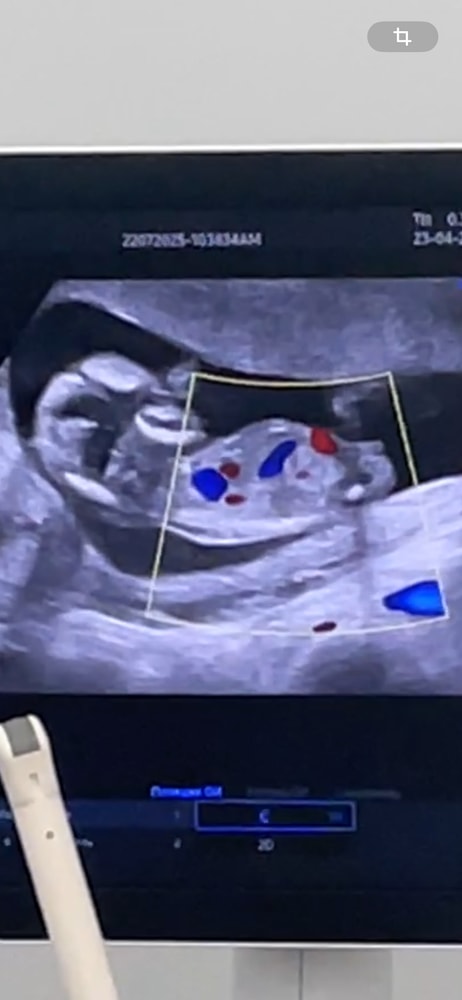

на 1 скрининге на сроке 12.4 недели

ктр 7,1см

Твп 2,8мм

срок по узи 13,2 недели.

все остальные показатели в норме. На узи напугали про твп чуть выше нормы.

Сильно страшно?